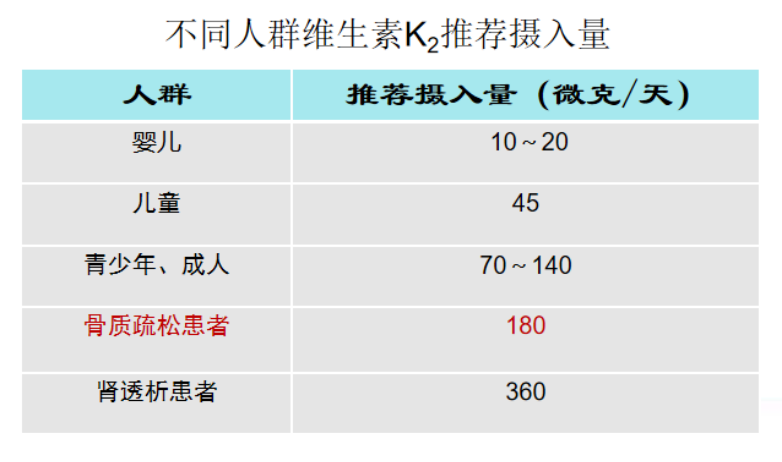

《中国人群骨质疏松症防治手册2013版》调查,中国95%以上老年人缺乏维生素K2。中国营养学会制定的膳食营养素参考摄入量:健康成人维生素K2的膳食适宜摄入量为50ug-120ug/d。具体情况请参照下表。